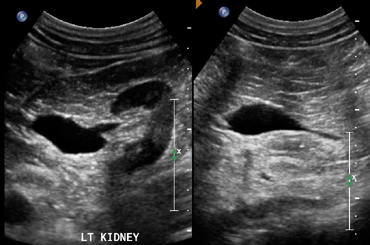

4-Extrarenal pelvis

هنا ببساطة يتواجد حوض الكلية خارج الكلية وكأنه كيس خارجي. الأهمية هنا تكمن في تمييزه بأنه تغير طبيعي وليس توسع في حوض الكلية أو كيس. التفرقة بينه وبين hydronephrosis تكون في عدم وحود توسع في calycis كما هو الحال في hydronephrosis.

في هذه الحالات يفضل التصوير بشكل transverse للتأكد.

5-Fetal lobulations

في مرحلة تطور الجنين تتكون الكلية عن طريق تلاحم عدة فصوص lobes. وهذه الفصوص قد تستمر إلى مابعد مرحلة البلوغ. تظهر بشكل تموجات في القشرة الخارجية للكلية. من المهم أن لا نخطئ في تشخصيها كندبة scar أو ورم في الكلية.